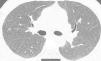

We report the case of a 41-year-old man, former smoker of 10 pack-years, who had worked as a precious stone polisher in a jewelry workshop for 20 years, using compounds containing a Be alloy. He lives in an urban setting, with no exposure to other inhaled substances. He was referred to the respiratory medicine department with a 4-month history of grade 1 dyspnea (MRCm), with no previous respiratory symptoms. Lung function study showed FVC: 4060ml (79%); FEV1: 3330ml (81%); FEV1/FVC: 82%; RV: 2430ml (116%); TLC: 6570ml (89%); DLCO: 26.7ml/min/mmHg (79%) and KCO: 4.84ml/min/mmHg/l (91%). Chest computed tomography identified a faint centroacinar nodular pattern of ground glass density, with poorly defined, bilateral diffuse edges, and slight predominance in the upper lobes. No increase in hilar or mediastinal node size was observed (Fig. 1). Transbronchial biopsy revealed areas of lung tissue with thin interalveolar septa, with no deposits, and foci of inflammatory infiltration with epithelioid cell accumulation, well-defined, without necrosis and with multinucleated cells, not containing foreign material. The bronchoalveolar lavage cell count was as follows: lymphocytes 90%, neutrophils 1%, macrophages 8%, eosinophils 0%, and a CD4/CD8 lymphocyte ratio of 4. Complete microbiological studies of the bronchial aspirate were negative.